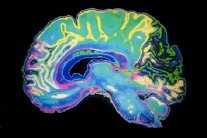

وبخلاف الكحول فان الماريجوانا لا تؤثر على حجم وسلامة المادة البيضاء أو الرمادية في الدماغ حتى بعد سنوات من تعاطيها.

والمادة الرمادية تمكن الدماغ من العمل في حين ان المادة البيضاء تتحكم بالاتصالات بين العناقيد العصبية. وقال مؤلف الدراسة البروفيسور كينت هاتشيسون من جامعة كولورادو بولدور الاميركية ان للماريجوانا ايضاً بعض الآثار السلبية ولكنها لا تُقارن بالآثار السلبية للكحول.